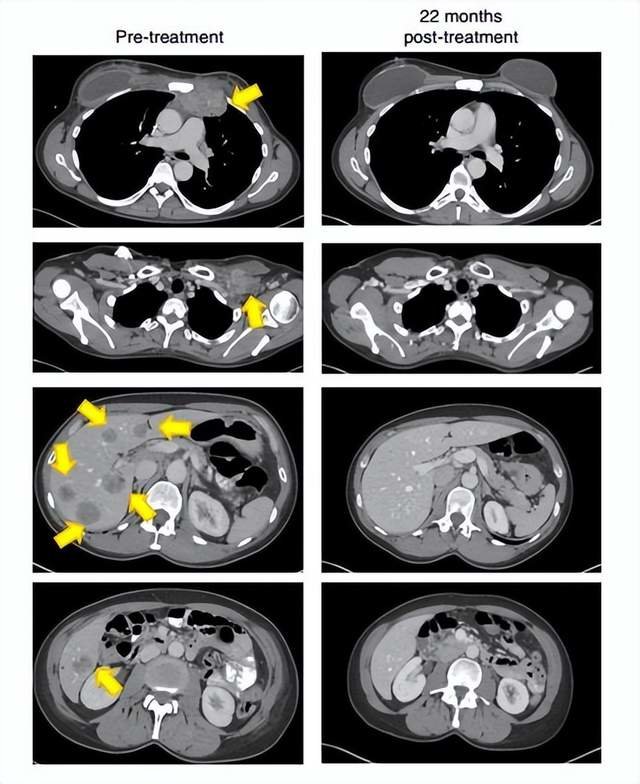

当900亿个免疫细胞被输入患者体内后,奇迹出现了。在6个月后的第一次随访时,患者的目标肿瘤负担锐减一半。而在治疗后的第22个月,从医学影像上看,所有肿瘤都消失了!

▲22个月后,这名患者的肿瘤(黄色箭头)消失得无影无踪(图片来源:《Nature Medicine》)